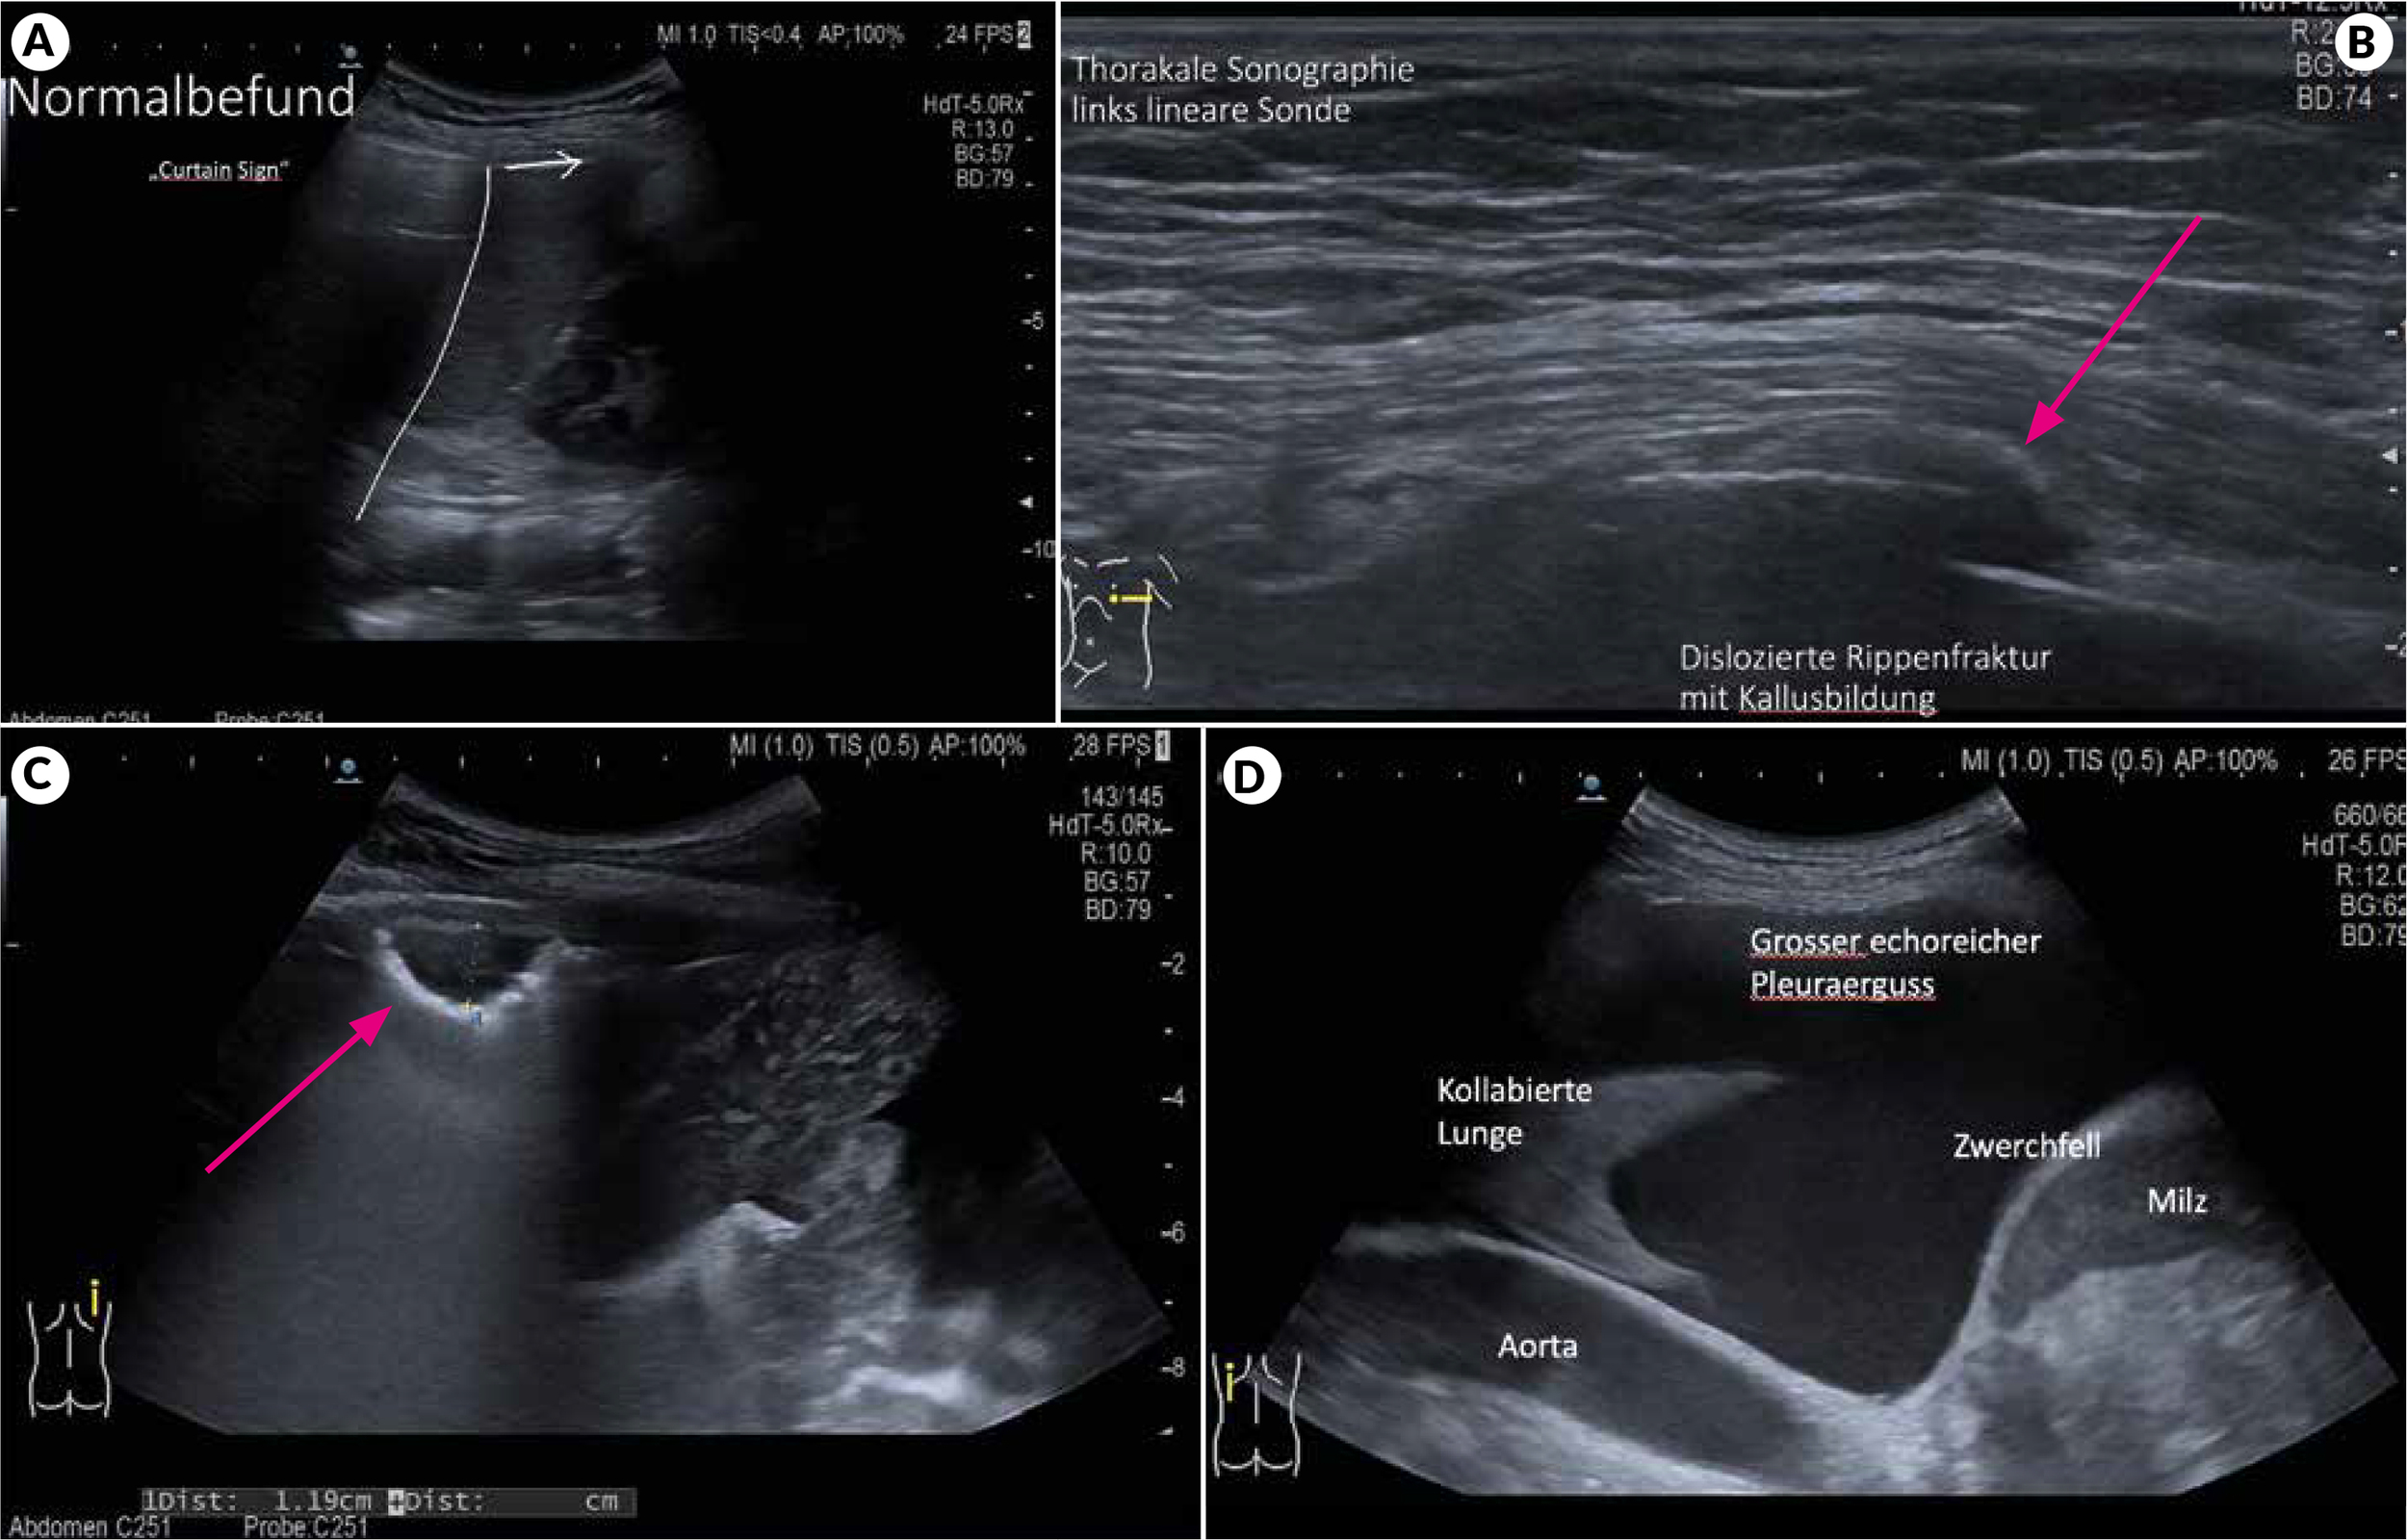

Ohne Pleuraerguss schiebt sich die luftgefüllte Lunge wie ein Vorhang «curtain sign» vor die Milz bzw. Leber (Abbildung 2A). Anhand des Bewegungsumfanges der Lunge kann auch die Zwerchfellbeweglichkeit mitbeurteilt werden. Die Pleura parietalis und die Lungenoberfläche mit Pleura viszeralis sind als helle echogene Linie sichtbar. Bei Inspiration und Exspiration zeigt sich das sogenannte «lung sliding» als gegenläufige Gleitbewegung der beiden Pleurablätter.

Rippenfrakturen

Die Diagnose einer Rippenfraktur mittels Thoraxröntgen ist unzuverlässig. Bei klinischem Verdacht bietet hier die thorakale Sonographie eine deutlich bessere Sensitivität (Abbildung 2B).4 Es empfiehlt sich mit der linearen Sonde dem Rippenverlauf zu folgen und die Rippen «abzufahren». Desweiteren sollte die Stelle maximaler Schmerzintensität vom Patienten bestmöglich lokalisiert und dort gezielt die Fraktur gesucht werden.

Thoraxwandtumore können in der Regel sehr gut mit der linearen Sonde detektiert und Lokalisation, Ausdehnung, Verschieblichkeit und Abgrenzung bzw. Kontakt zu Thoraxwandstrukturen spezifiziert werden (Abbildung 2C). Dies erlaubt zumeist auch eine direkte ultraschall-geführte Feinnadelaspiration, da keine belüftete Lunge durchstochen werden muss. Hierzu wird nach Lokalanästhesie die Punktion in der Regel mit einer 22G (Spinal-)Nadel mit Mandrin durchgeführt und mit Sog über eine 10 ml Spritze zytologisches Material asserviert. Oftmals erlaubt das zytologische Feinnadelaspirat eine Zuordnung der zugrundeliegenden Pathologie und kann auch für weitere Analysen herangezogen werden. Bei unzureichendem Material für eine präzise Diagnose (ggf. inklusiv molekulargenetischer Analytik) kann ebenfalls ultraschall-geführt eine grössere Gewebeprobe zur histologischen Analyse mittels Schneidbiopsienadel (z.B. mittels True-Cut/ Bio-Pince) entnommen werden.5

Pleuraergüsse können mit Ultraschall deutlich besser diagnostiziert und quantifiziert werden als mittels konventionellem Röntgen.7 Ein Pleuraerguss stellt sich typischerweise als homogener, echoarmer Bereich zwischen den beiden Pleurablättern dar. Bei grösseren Ergüssen kann oft auch eine haifischflossenartige atelektatische Lunge dargestellt werden (Abbildung 2D). Für die Quantifizierung der Ergussmenge hat sich eine einfache, zuverlässige Formel bewährt: Dazu wird die maximale kraniokaudale Ergussausdehnung in sitzender Position im Bereich der lateralen Thoraxwand gemessen. Die maximale Ergussausdehnung in cm ergibt mit 100 multipliziert die abgeschätzte Ergussmenge in ml.